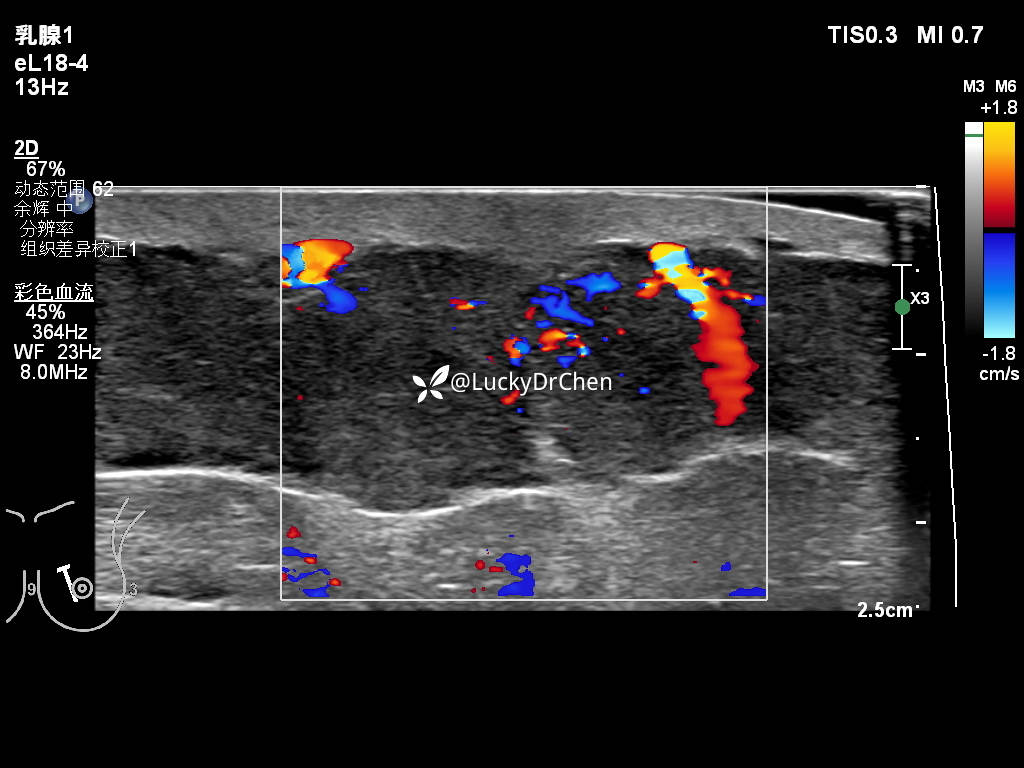

脂肪层血流信号增多